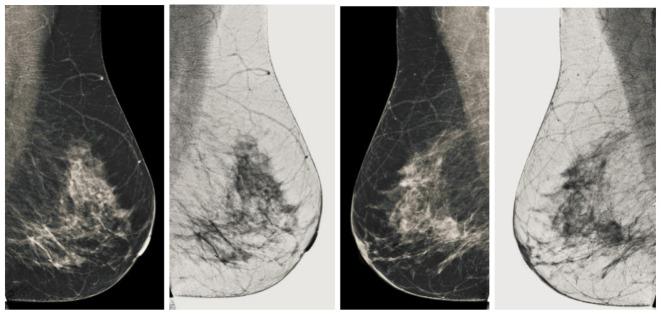

Breast cancer is widespread around the world and can be cured if diagnosed at an early stage. Digital mammograms are used as the most effective imaging modalities for the diagnosis of breast cancer. However, mammography images suffer from low contrast, background noise as well as contrast as non-coherency among the regions, and these factors makes breast cancer diagnosis challenging. These problems can be overcome by using a new image enhancement technique. The objective of this research work is to enhance mammography images to improve the overall process of segmentation and classification of breast cancer diagnosis. We proposed the image enhancement for mammogram images, as well as the ablation of the pectoral muscle. The image enhancement technique involves several steps. In the first step, we process the mammography images in three channels (red, green and blue), the second step is based on the uniformity of the background on morphological operations, and the third step is to obtain a well-contrasted image using principal component analysis (PCA). The fourth step is based on the removal of the pectoral muscle using a seed-based region growth technique, and the last step contains the coherence of the different regions of the image using a second order Gaussian Laplacian (LoG) and an oriented diffusion filter to obtain a much-improved contrast image. The proposed image enhancement technique is tested with our data collected from different hospitals in Qassim health cluster Qassim province Saudi Arabia, and it contains the five Breast Imaging and Reporting System (BI-RADS) categories and this database contained 11,194 images (the images contain carnio-caudal (CC) view and mediolateral oblique(MLO) view of mammography images), and we used approximately 700 images to validate our database. We have achieved improved performance in terms of peak signal-to-noise ratio, contrast, and effective measurement of enhancement (EME) as well as our proposed image enhancement technique outperforms existing image enhancement methods. This performance of our proposed method demonstrates the ability to improve the diagnostic performance of the computerized breast cancer detection method.